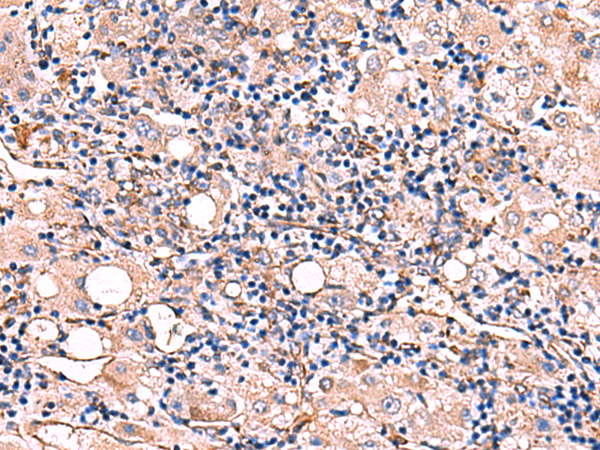

分类: 科研抗体货号: P07134别名: ALK6; ALK-6; CDw293应用: IHC反应种属: Human, Mouse